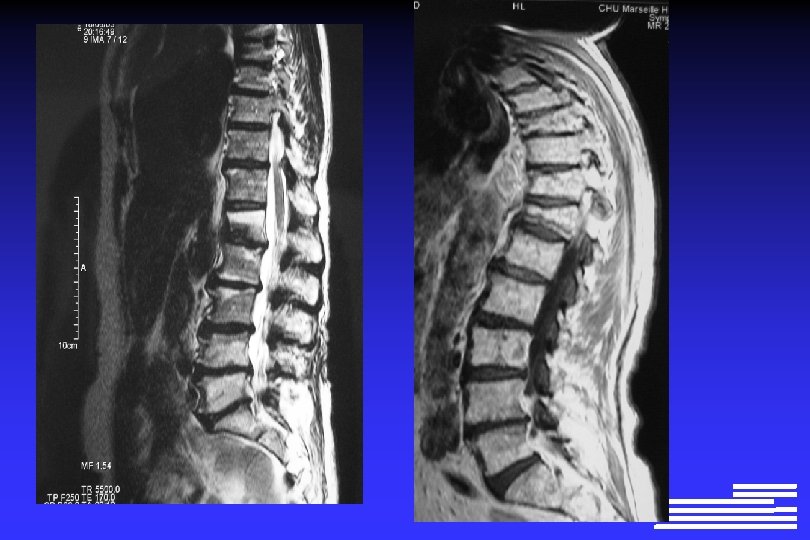

Explorations à effectuer pour le diagnostic positif et différentiel l Radiographie du squelette complet Ø Lésions lytiques à l’emporte-pièce Ø Lésions « ostéoporose diffuse » Ø Lésions condensantes (rares +++ !, 0, 5 à 3% des cas)